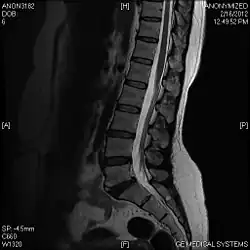

T2 W Sagittal image

A limbus vertebra is a bone tubercle formed by bone trauma on a vertebral body, bearing a radiographic similarity to a vertebral fracture. The anterior-superior corner of a single vertebra is the common site for this defect although it can also be seen at the inferior corner as well as the posterior or anterior margin. Anatomically, it is assumed to be an intra-vertebral body herniation of the disc material occurring during adolescent growth spurt when the ring apophysis has not yet fused. It was first described by Schmorl in 1927[1] and later in detail by Leif Sward and Adad Baranto.

Viewed in a lateral radiograph, it appears as a triangular shaped bone fragment, not unlike an anterior lip fracture, but with softer edges.

Limbus vertebra is not always symptomatic, but severe cases may lead to more serious pathological conditions and chronic pain. In rare instances, a posterior limbus vertebra has been described causing radiculopathy due to nerve root compression. [2]